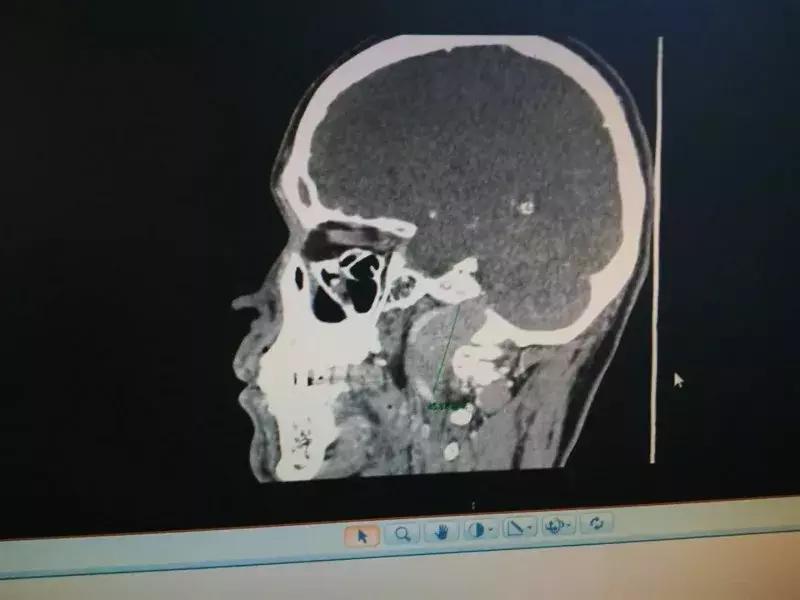

57岁的老马因连续多年头晕发麻、舌头歪斜、说话和进食困难,到河南省人民医院口腔颌面外科就诊。经过仔细检查,本来以为没多大事的老马一家被检查结果吓坏了——颅底有一个鹅蛋大肿瘤。

手术的难度在于肿瘤位于颅底、颞下窝及翼腭窝,并且侵犯了部分颅骨而突入颅内。该处解剖结构复杂,包含众多的大血管及重要神经。

彭利伟解释说,因为肿瘤侵犯了患者一部分颅骨,导致肿瘤正处于漏斗状的“深井”里,且肿瘤的体积明显比“井口”大,给整个切除手术增加了不少困难。

更危险的是,根据影像检查结果,肿瘤还“侵吞”了一根颅内动脉,长度超过10厘米。

经过测量,肿瘤体积为5.5厘米×8厘米×4厘米,重量超过500克。